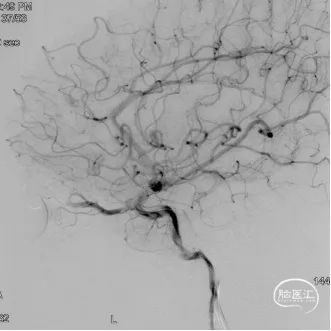

术前造影

双侧颈内动脉正侧位造影见前颅窝底硬脑膜动静脉瘘,双侧筛前动脉、筛后动脉向瘘口供血,通过皮层静脉向上矢状窦引流。

双侧颈外动脉正侧位造影见镰前动脉向瘘口供血。

左侧椎动脉正侧位造影未见明显异常。